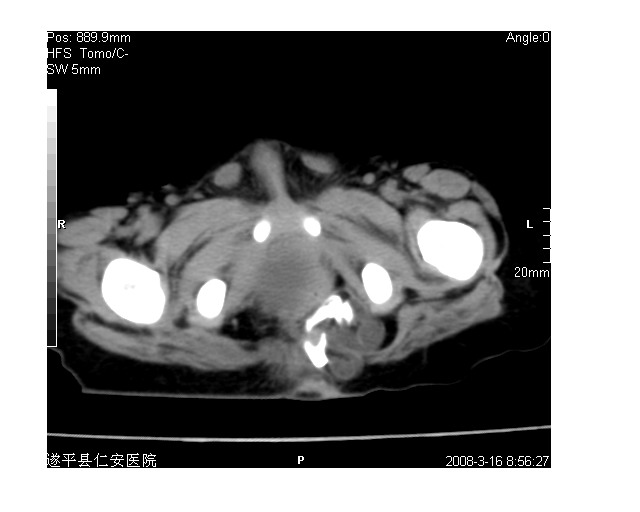

以下是引用lkc8963在2008-3-16 12:49:00的发言:[br]盆底巨大混杂密度肿块,富含多种组织成分包括脂肪/液体/软组织/钙化,边界清楚,向前压迫肠管及膀胱,向后突入骶尾部皮下脂肪层,首先考虑畸胎瘤,诊断时需要与脊柱裂/囊性淋巴管瘤等区别。